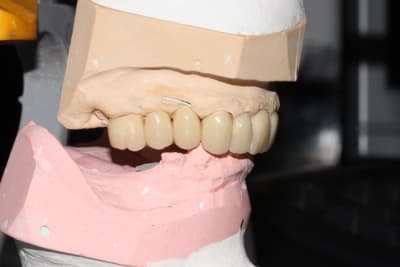

Le jour de l'empreinte des IC, on prend également une empreinte alginate du bridge pro en place.

Ainsi, par CFAO et en se basant sur les tissus mous périphériques, le labo nous a confectionné un duplicata du bridge pro en résine usinée, qui nous servira à enregistrer la RIM définitive: je n'aurai aucune retouche à y apporter.

Puis classique essayage d'armature (parfaite, merci le labo), et pose. Réglages occlusaux le lendemain.

Photos de l'occlusion avant les réglages occlusaux, tout juste sorti du labo. J'ai diminué les contacts sur la 23 en entrée de cycle, et sur la 21 en incision. (bleu en statique, rouge en cycles masticatoires)